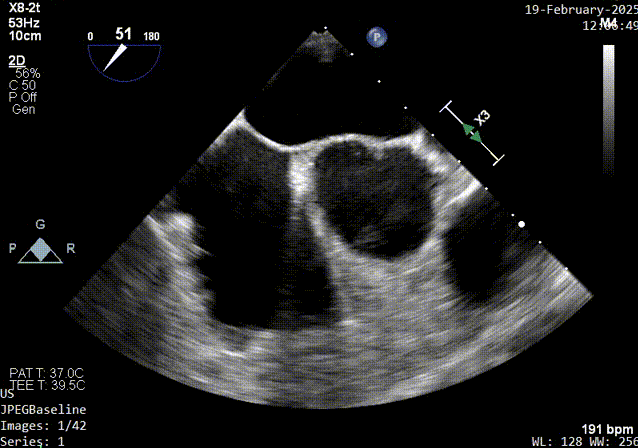

主动脉短轴切面超声影像

1、PFO结构:巨大型PFO,静息状态下房水平左向右分流。继发隔厚约5.7mm;原发隔厚约1.2mm;未见明确下腔静脉瓣及希阿里网回声。

2、PFO参数:隧道裂隙宽约4.4mm ;卵圆孔隧道长度14mm;